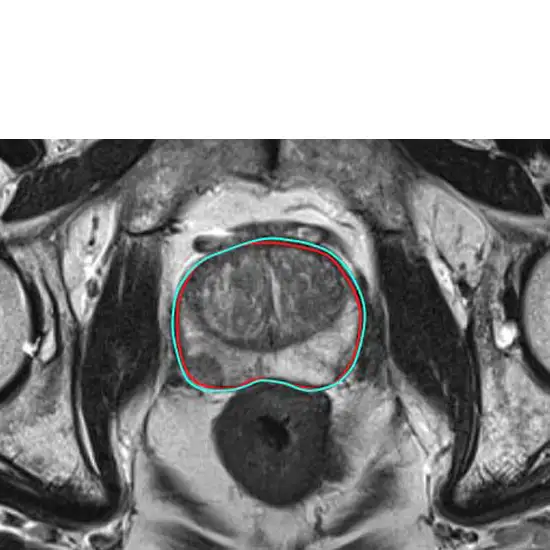

MRI Prostate

MRI Prostate is a magnetic resonance imaging test in which a magnetic field, radiofrequency pulses, and a computer is used. Doctors use this diagnosis mainly to evaluate the extent of prostate cancer.

MRI prostate is the magnetic resonance imaging technique that produces images of the prostate, that help in the diagnosis of prostate cancer or other problems related to the prostate gland.

MRI prostate scan is widely used to detect prostate cancer, its spread, and possible complications that might interfere with the treatment of prostate cancer. The MRI prostate scan can also help monitor the efficacy of the ongoing cancer treatment and recurrence of the prostate cancer.

MRI prostate is a safe, non-invasive, and accurate diagnostic technique with a sensitivity of 70.7%-85.9%, a specificity of 46.8%-77.3%, and an accuracy of 54.6%-80.1%.